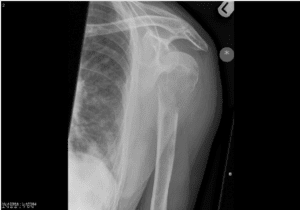

A 94-year-old woman has a deep gnawing pain in her left arm. She has had a 10 kg weight loss in the past year. Her temperature is 37.3°C. She has localised tenderness over the left upper arm. Investigations: X-ray left arm (see image).

Which is the most likely cause of her pain?

The most likely cause of the 94-year-old woman’s pain in her left arm is metastatic carcinoma. She has lost weight, and the site of the abnormality, i.e., proximal humerus, is a common site for metastasis. The X-ray is consistent with metastatic carcinoma.